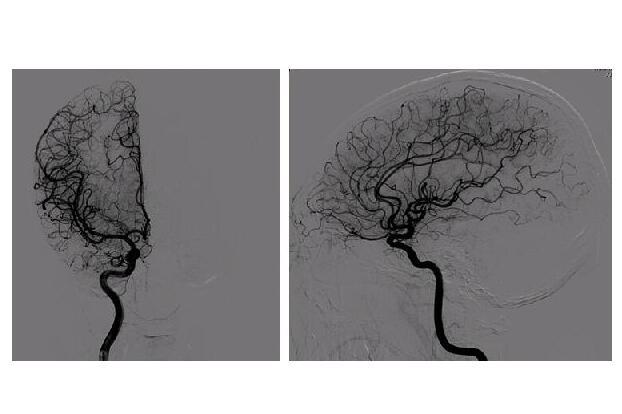

第二,手术的方式不一样。输卵管通水将药水打到输卵管里面去以后,医生就会感觉到输卵管是否通畅。另外,它还对输卵管有一种治疗的作用。输卵管造影是将造影剂打入输卵管以后,需要用x线拍片,在拍片下可以清楚的看到输卵管以及盆腔有没有造影剂显影。所以输卵管造影要比输卵管通水准确得多。

输卵管造影危害并不大,只要在术后根据医生的指导,一般不会对身体产生很大的影响。输卵管造影术是在输卵管内注入造影剂,主要是可以检查输卵管是否通畅,并且能够有效的确定输卵管堵塞的部位和堵塞的程度。